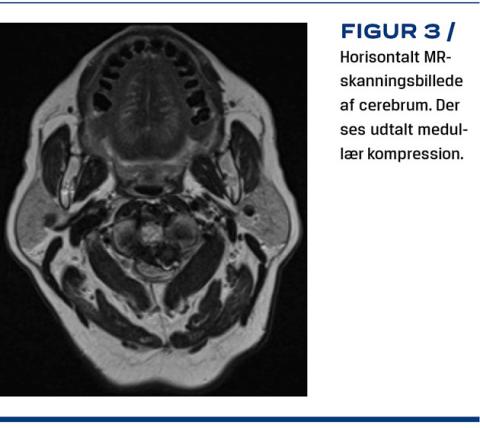

De hyppigste symptomer er lokale nakke- og hovedsmerter, nakkestivhed og torticollis [15, 17]. Derudover forekommer der unormal atlantoaksial bevægelse og cervikal instabilitet. Instabilitet kan være anterior eller posterior og i nogle tilfælde ikke identificerbar. Ved anterior instabilitet sublukserer C1 ventralt i relation til C2 med risiko for dorsal kompression af rygmarven forårsaget af arcus posterior af C1. Posterior instabilitet ses specielt ved ekstension af nakken, hvor knoglefragmentet glider dorsalt med risiko for ventral kompression [5, 18]. Cervikal medullær kompression er yderst alvorlig pga. dens placering og dertil hørende risiko for føleforstyrrelser, nedsat muskelkraft og i værste fald lammelser, kredsløbssvigt og død [1, 5]. Sekundært til instabilitet ses dannelse af pannus (Figur 2). Pannus er noninflammatorisk væv, der opstår ved øget mekanisk belastning som udtryk for instabilitet og øger risikoen for medullær kompression (Figur 3) [19]. Nogle symptomer ses jævnligt i forbindelse med andre lidelser, f.eks. reumatoid artritis og spondylose, hvorfor OO let overses og først identificeres, efter at der er foretaget billeddiagnostik [3].